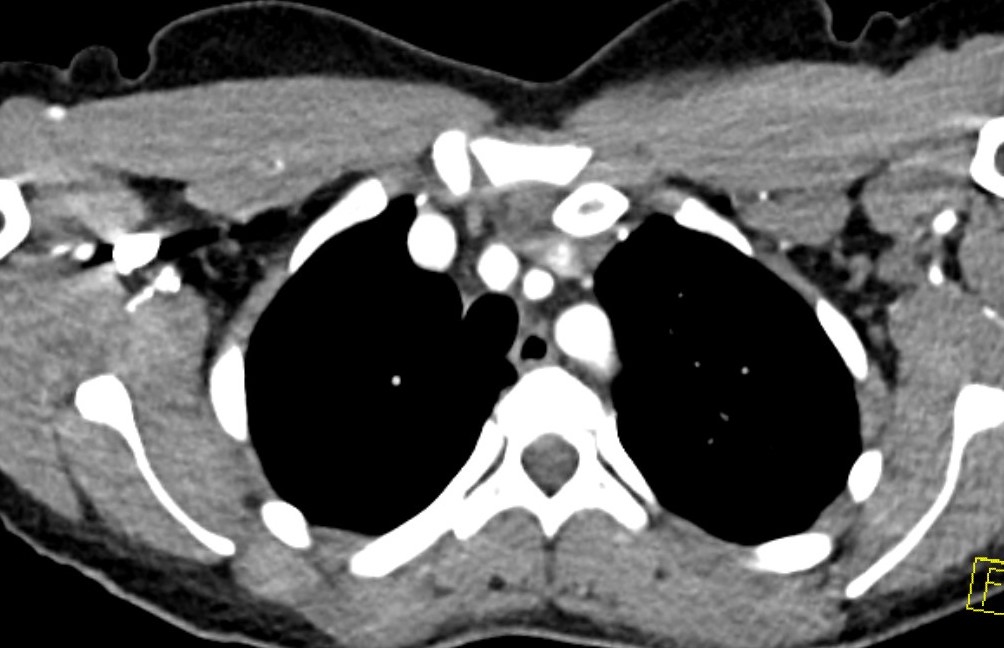

CT scan

Left posterior SCJ dislocation with pre- and post angiogram

Severe left posterior SCJ dislocation with subclavian vein compression